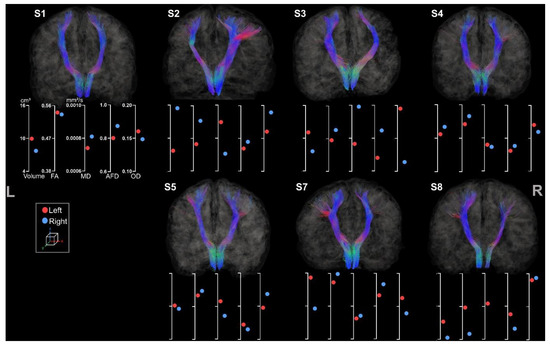

3.3.1. Medio-Lemniscal Tracts Extraction